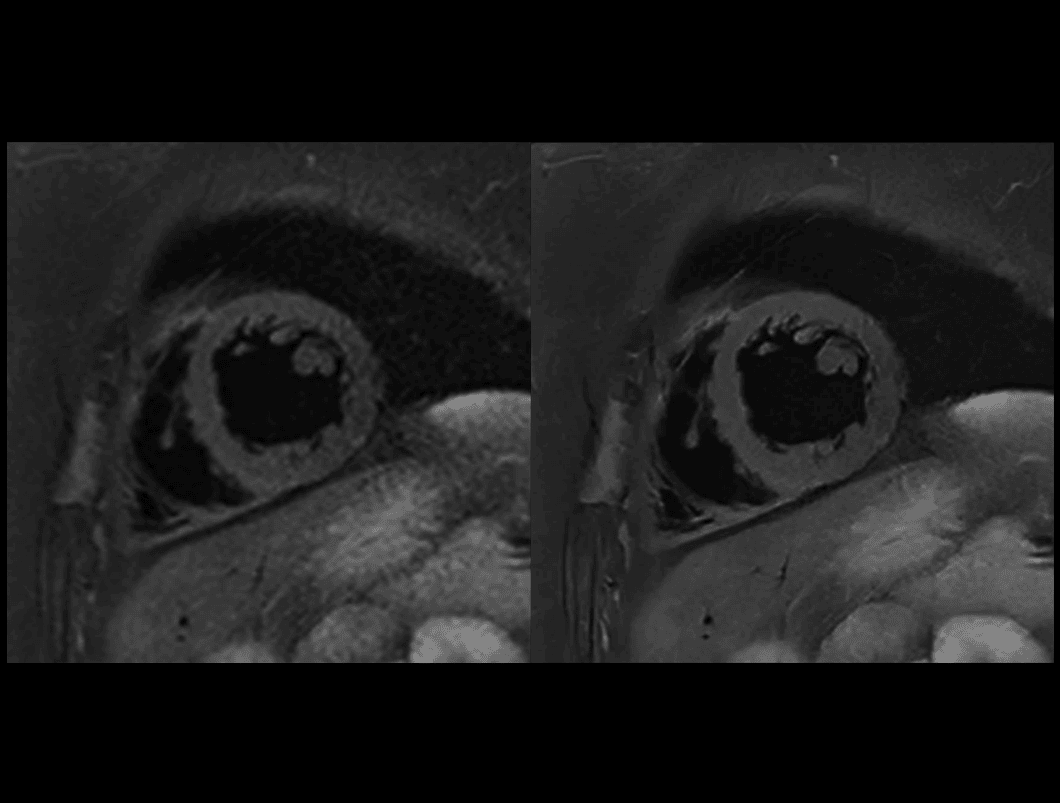

Cord T2W DB SPAIR

Comparație între tehnica convențională (9,4 sec) și uAIFI DeepRecon™ (9,4 sec), cu rezoluție de 0,78 × 0,78 × 4 mm³, evidențiind claritatea superioară și acuratețea detaliilor obținute prin reconstrucția AI.